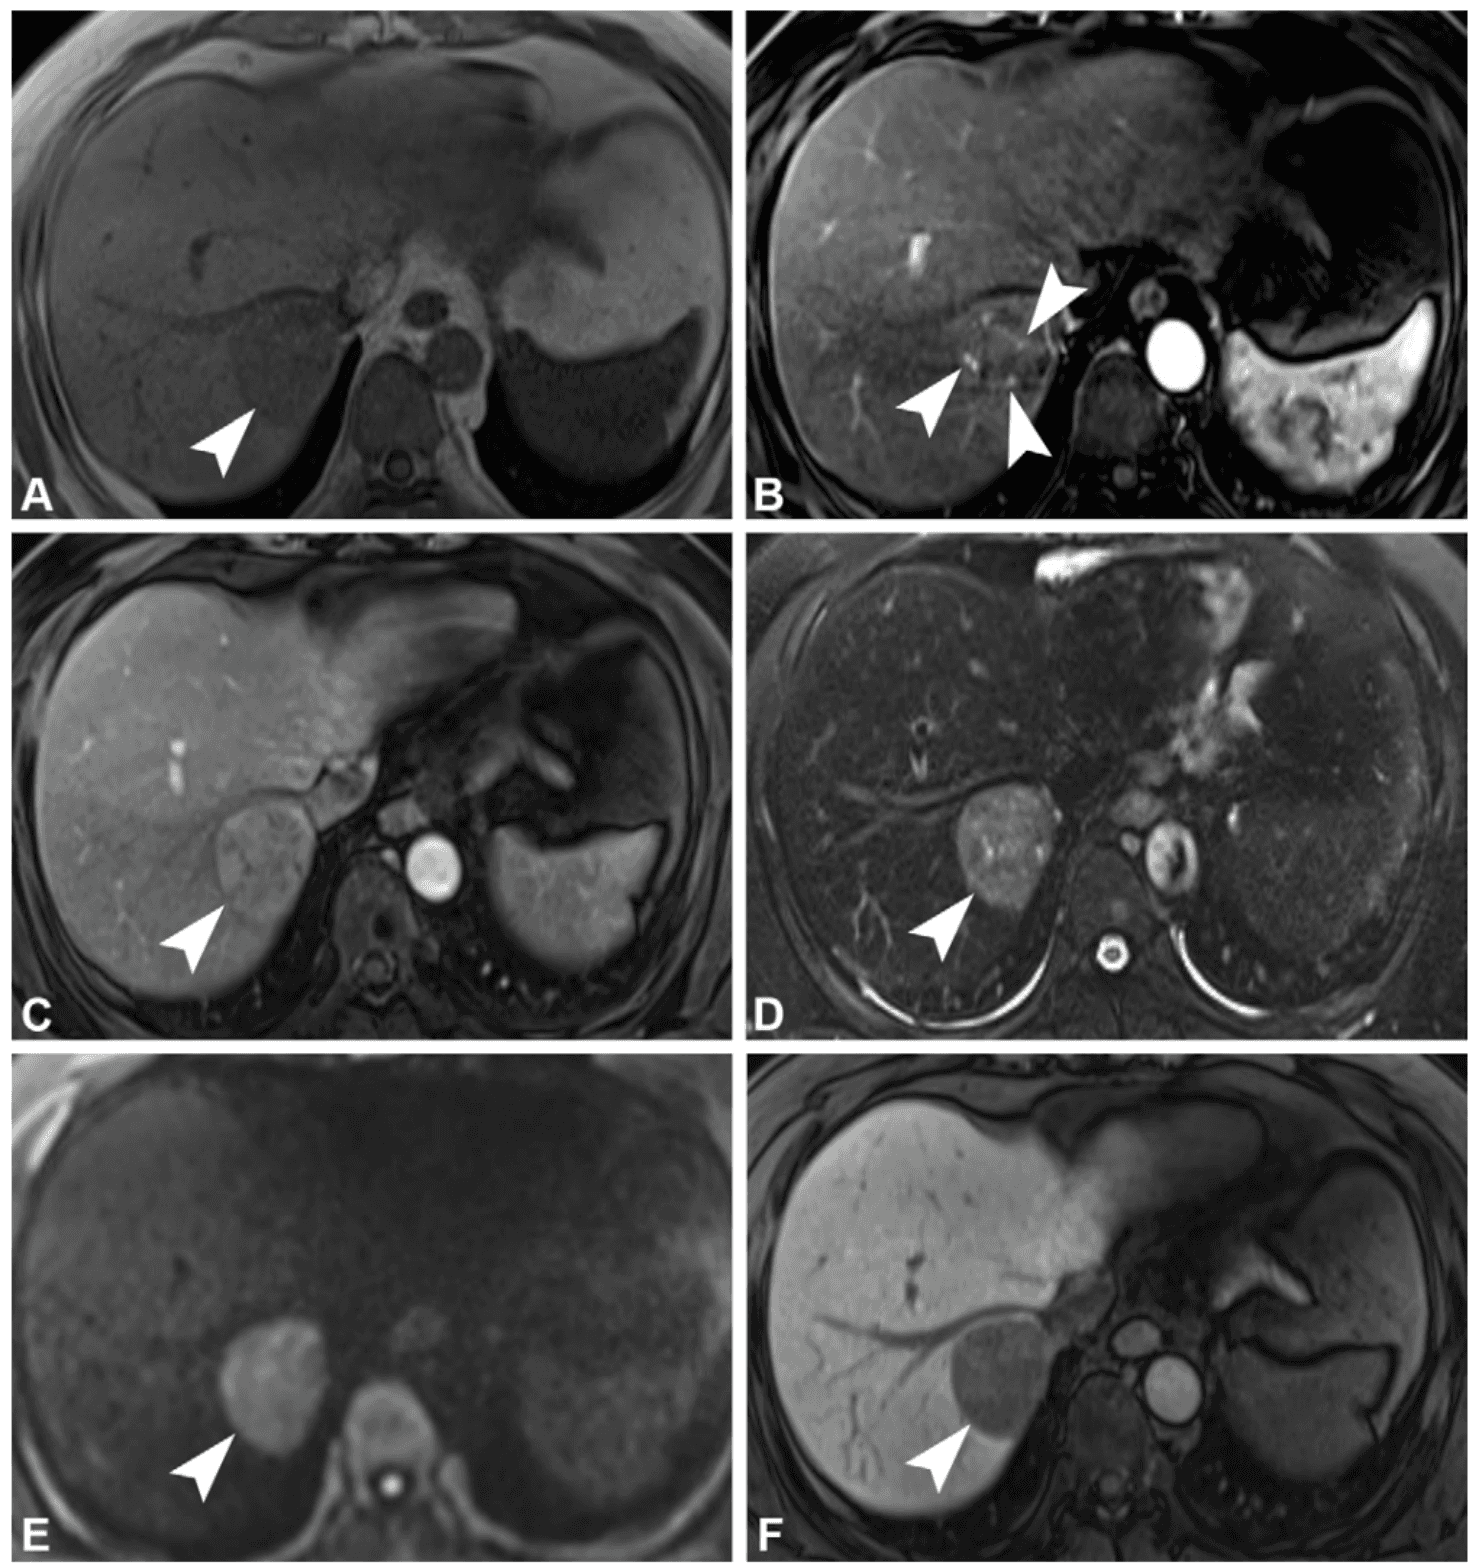

MERIS combina variables clínicas y radiológicas con peso pronóstico claro: AST > 29.5 IU/L (+2), tamaño tumoral en centímetros (+1 por cm), margen tumoral no liso (+2) e hipointensidad peritumoral en fase hepatobiliar (+3). Juntas, estas variables permiten construir un riesgo individualizado de recurrencia temprana y distinguir tumores aparentemente pequeños pero biológicamente agresivos.

La hipointensidad peritumoral en fase hepatobiliar es el hallazgo más robusto del modelo. Su presencia sugiere alteración de transportadores OATP vinculada a obstrucción de vénulas portales por células tumorales. En términos clínicos, es una señal funcional de invasión microvascular antes de que ésta sea visible al microscopio.

En la validación externa, MERIS alcanzó un C-index de 0.75, por encima del modelo basado en patología PERIS (0.67), y también superó a sistemas tradicionales como BCLC y CLIP en esta población de CHC pequeños. Esto importa porque, en tumores con rango de tamaño estrecho, la sola morfología deja de ser suficiente para explicar el pronóstico. MERIS introduce una lectura más fina: la agresividad tumoral puede estar escrita en la imagen mucho antes del reporte histológico.

Uno de los errores más frecuentes es asumir que una lesión ≤ 2 cm representa automáticamente bajo riesgo. Otro es concentrar el análisis solo en el nódulo tumoral y omitir la zona peritumoral en fase hepatobiliar. Justo ahí reside buena parte del valor pronóstico real de MERIS.

La utilidad real de MERIS aparece cuando transforma la discusión terapéutica. Un score acumulado > 5 identifica al grupo de alto riesgo: la probabilidad de permanecer libre de recurrencia a 2 años cae de 87.4% en bajo riesgo a 59.3% en alto riesgo. Este dato puede reordenar la estrategia: ampliar la resección, discutir una resección anatómica, considerar trasplante primario o priorizar vigilancia y terapias adyuvantes con mayor precisión.